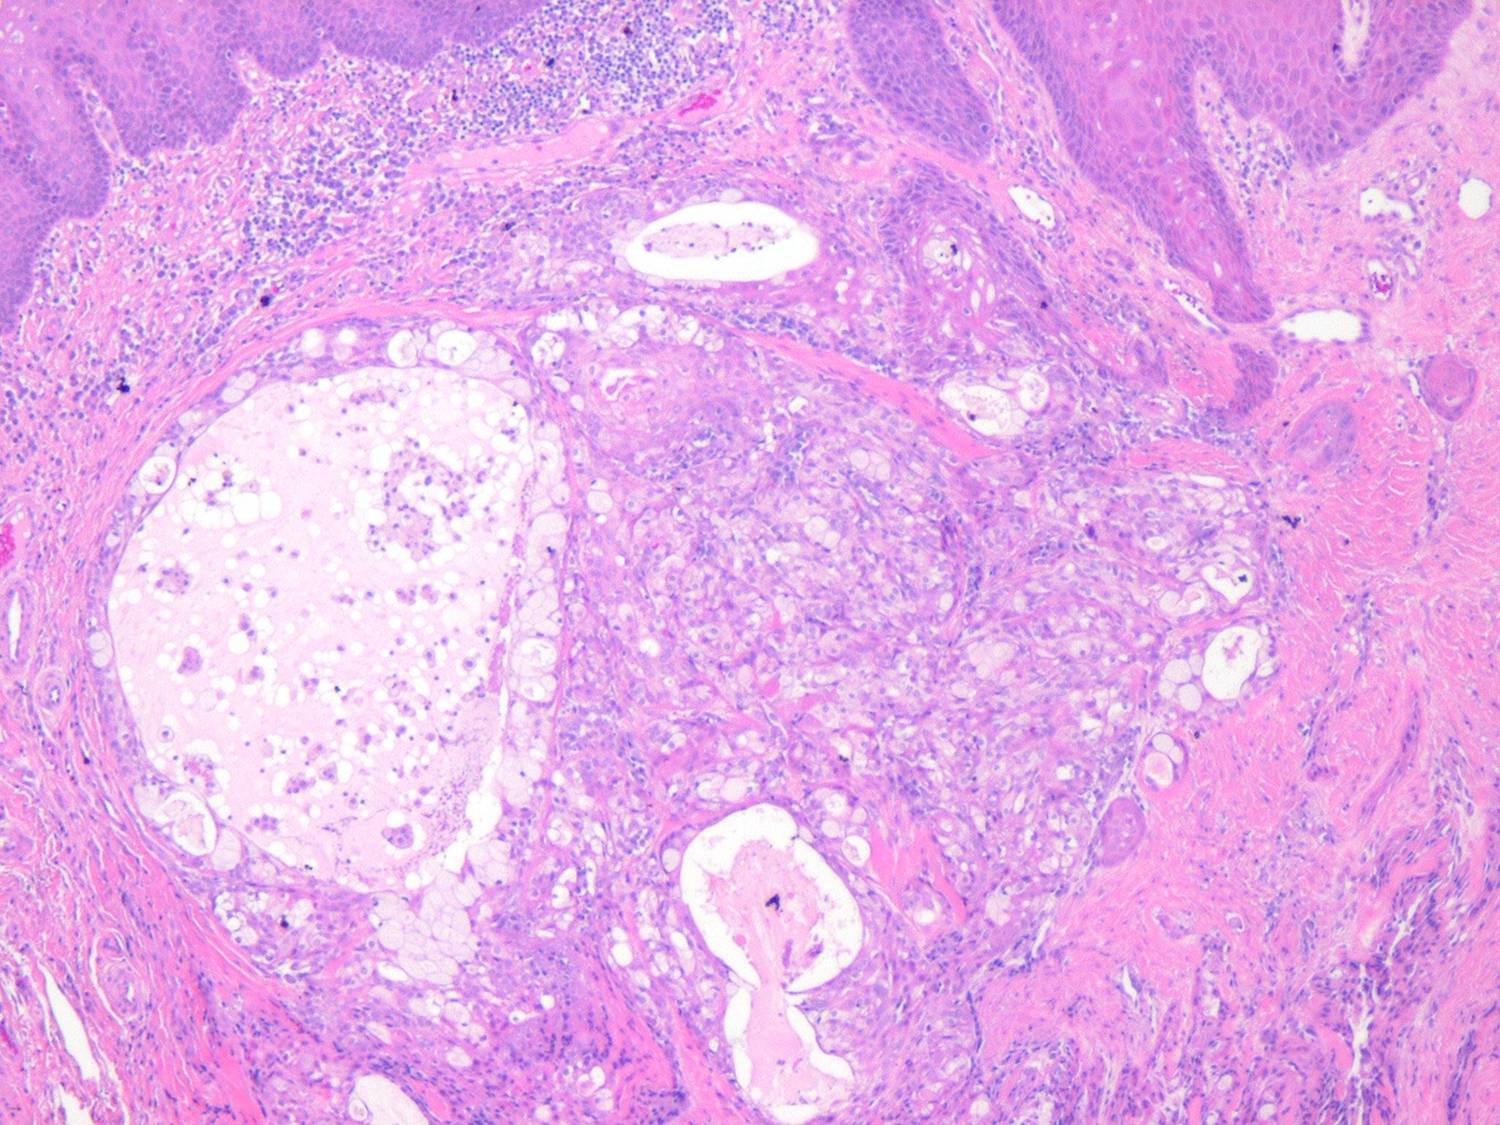

Mucoepidermoid carcinoma =الكارسينوما المخاطية البشروانية